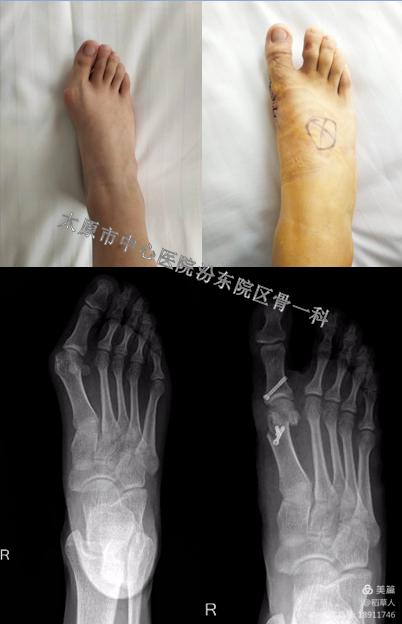

这是一位24岁的年轻女孩,经过手术后成功恢复了美丽的外观。